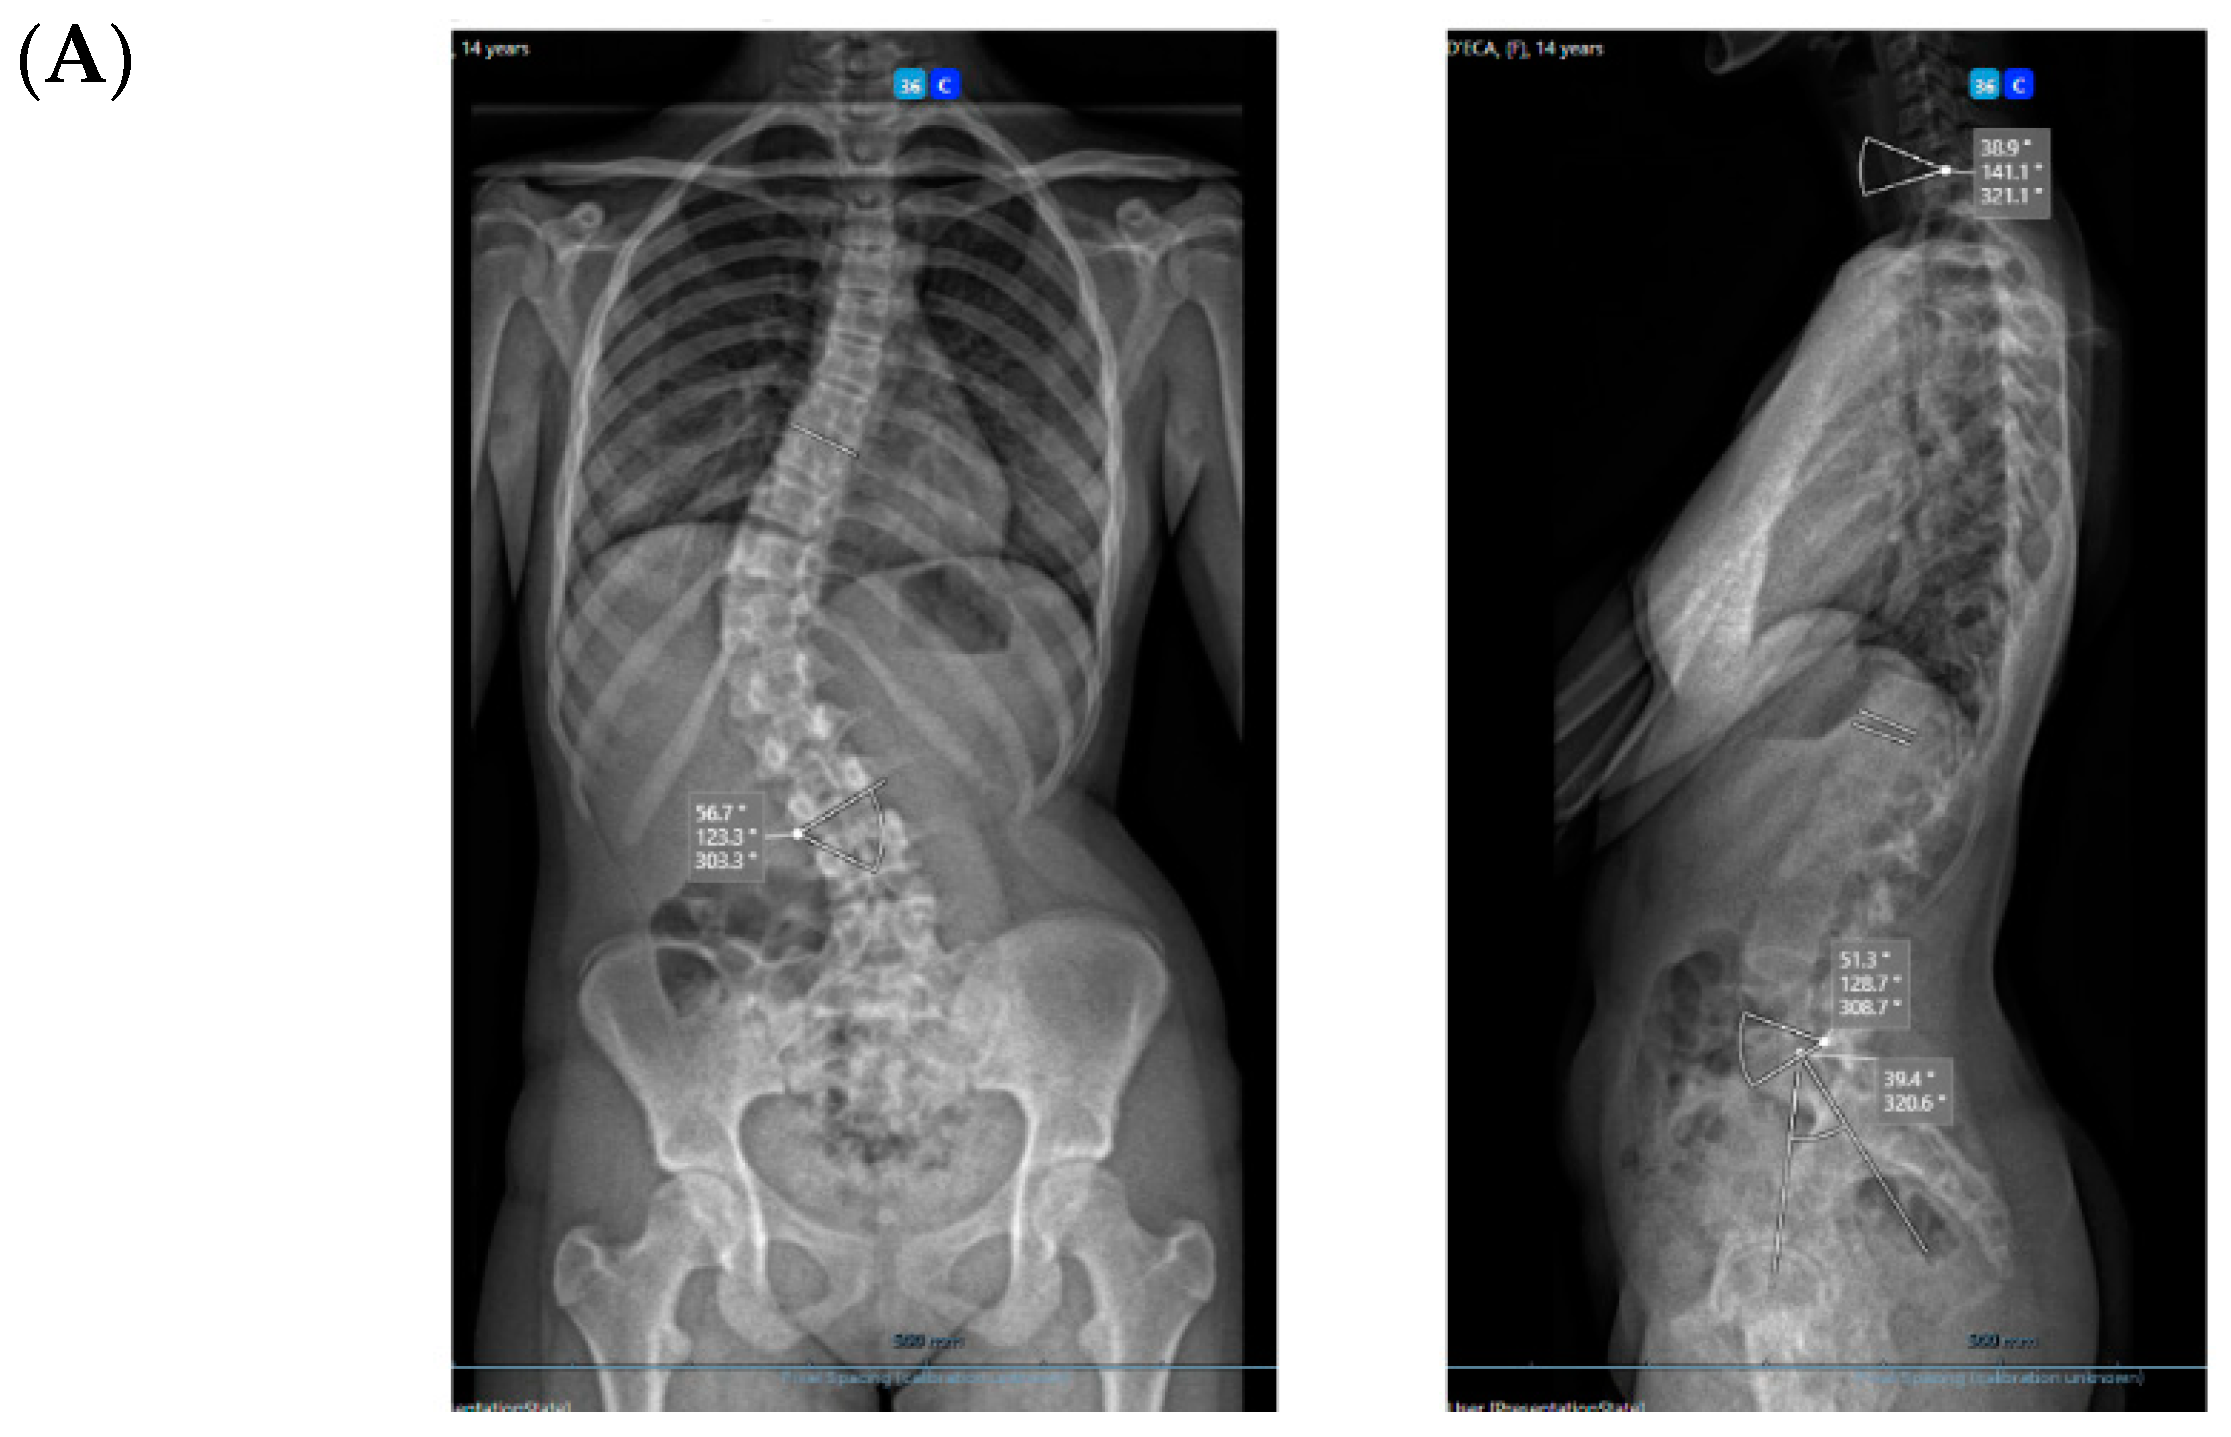

All three cases were thoracolumbar scoliosis (Lenke 5C) with an apex between T12 and L1 (Figure 3, Figure 4 and Figure 5).

Figure 3.

A 14-year-old adolescent. (A) Pre-op. (B) Immediate post-op. (C) One-year follow up.

As far as skeletal maturity is concerned, two cases were Sanders 3 (Risser 1 and 0) and one case was Sanders 5 (Risser 4).

All cases have progressed well with improvement of the curvatures with growth (Table 1) both in the coronal and sagittal alignment. At the 6-month FU, there was a mean 67.5% (34.8°) improvement in the main Cobb angle, but at 1 y, the oldest case over-corrected, and this was clinically noted by the girl, who pointed out that her flank symmetry had recently inverted (from one side to the other) after being symmetrical for some time (Figure 6).

Spinal growth is difficult to assess accurately in a coronal deformity that is gradually improving by the surgical procedure in a spine that is still growing, as the two chosen spots will gradually distance away from each other through these two mechanisms. We have taken the same midpoint in the distal endplate of the instrumented vertebra or on the proximal endplate, which is always on the same proximal junctional vertebra (Figure 8). Over this period of 6 months, the referred distance has increased by a mean of 7 mm (min. 3–max. 16 mm) in the three cases, and the oldest girl (56.7° Cobb angle pre-op) saw the greatest increase. In the case of such flexible scoliosis with a more severe Cobb angle that corrected significantly with this technique (Figure 8 and Figure 9), it is obvious that the two chosen spots will distance more from each other than in scoliosis with a smaller Cobb angle. This increase in spinal length between the two endplate spots is not spinal growth per se, but differentiating these two mechanisms is difficult.